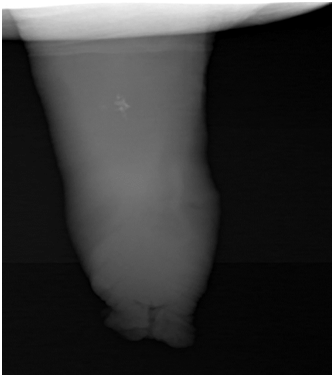

A 48year old male patient , a known diabetic presented with a palpable hard nodular lesion in the middle third of penis since 6months. Local USG of penis showed linear echoreflective calcified plaque in intercorporeal septum extending along the ventral aspect of bilateral corpora cavernosa causing posterior acoustic shadowing (Figure 1A & Figure 1B). A diagnosis of Peyronie’s disease was made. Plain radiograph of penis done with soft tissue exposure confirmed calcification (Figure 2).

Figure 2 Radiograph of penis with soft tissue exposure showing multiple calcific plaques in mid penile shaft.